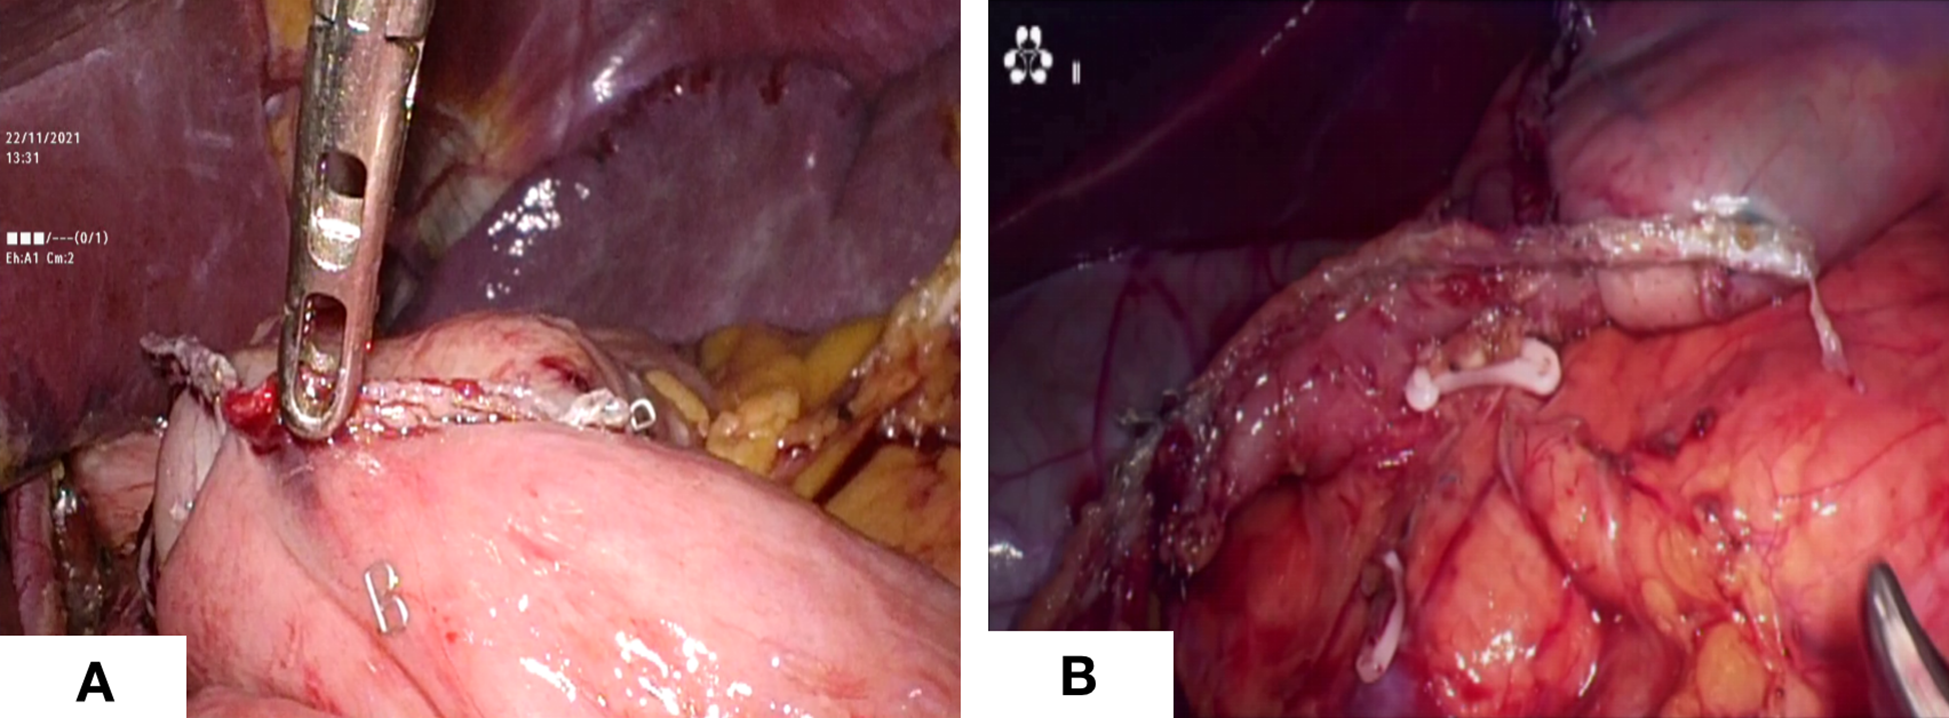

Figure 3

Digestive tract reconstruction. (A) Billroth -I anastomosis; (B) Billroth - II anastomosis.

The sequences of perigastric lymph node dissection vary, and some unique procedures need to give priority. Firstly, the omentum was lifted using duckbill forceps in the left hand and the mesocolon was dissected using a harmonic in the right hand. It is significant for the surgeon to create the working field by fully using the pulling effect of both hands. The anatomy-based approach made lymph node dissection easier. Then, the right side omentum and gastric tissue were transferred to the left to fully expose the gastroomental arteriovenous area (Figure 2A). In the meanwhile, the non-working surface of the ultrasonic knife was close to the splenic artery and tentatively picked up the lymphatic tissue on the blood vessel wall to clean the lymph nodes, which prevented blood vessel from being damage. Finally, the gauzes strip can be blocked on the posterior wall of the stomach to block the stomach and omentum. The left hand maintained a certain tension, and the right-hand ultrasonic knife carried out naked cleaning along the blood vessels. The delta-shaped anastomosis was used both in Billroth - I (Figure 3A) and Billroth – II anastomosis (Figure 3B) in operation.